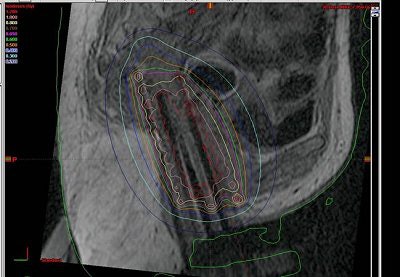

"We then have the radiologist look at the series of MR images obtained and reposition the obturator so that the needles were directed at the tumor," Viswanathan explained. "We then do the insertion on real-time MR guidance. It doesn't mean that as we are putting in the needles, we are seeing them go in. It does mean that we put the needles in, scan the patient in ... axial or sagittal planes, look at where the needle is, and readjust. Then we get final MR imaging after all the needles have been inserted and we're happy with our tumor volume."

| No inadvertent insertion of interstitial catheter into bladder or rectum noted on CT (below) after MR (above). |

The patients' legs were then brought down and they were reimaged for the CT simulation. "We learned that it was very important to image with the legs down. There was substantial movement with the legs down. But once we figured that out, we were able to perfectly reconstruct the images so that the catheters lined up on MR," Viswanathan said.

The results showed that protection of the bladder and rectum was achieved. In all 10 cases, there was no inadvertent insertion.